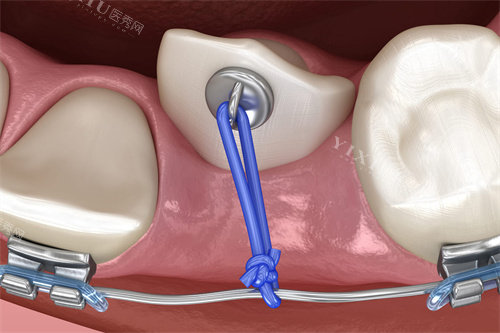

“凌晨两点牙疼到哭,直接打车冲到浙大口腔!”市民林女士回忆道,“急诊医生检查后说是急性牙髓炎,立刻做了开髓引流,疼了半小时就缓解了!”

作为浙江省口腔医疗的“顶梁柱”,浙大口腔的急诊科全年无休,24小时接诊。无论是牙齿断裂、剧烈疼痛,还是颌面部外伤出血,这里都能快速处理。医院位于拱墅区武林路,夜间急诊通道畅通,标识清晰,即使深夜也能快速找到。

“孩子晚上摔跤磕断门牙,急得我手抖,亮贝美口腔的医生用树脂修复后,几乎看不出痕迹!”市民周女士说,“医生还教我怎么保存断牙,说如果保存得当还能再接回去。”

亮贝美口腔是专科二级医院,夜间营业至20:00,擅长处理牙外伤、急性牙痛等急症。医院位于滨江区星光时代广场,交通便利,适合住在附近的居民。